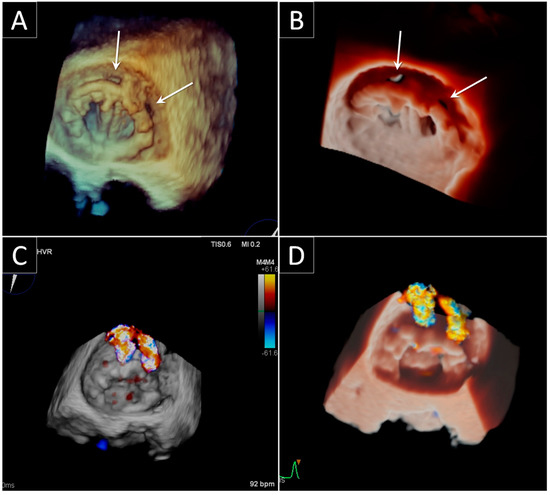

3.2. Aortic Paravalvular Leak